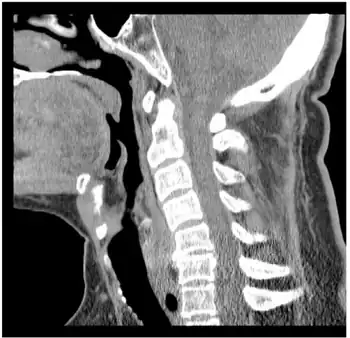

Because PPS can fatigue facial muscles, as well as cause dysphagia (difficulty swallowing), dysarthria (difficulty speaking) or aphonia (inability to produce speech), persons may become malnourished from difficulty eating. Compensatory routines can help relieve these symptoms, such as eating smaller portions at a time and sitting down whilst eating.[15] PPS with respiratory involvement requires exceptional therapy management, such as breathing exercises and chest percussion to expel secretions (clearing of the lungs) on a periodic basis (monitored via stethoscope). Failure to properly assess PPS with respiratory involvement can increase the risk of overlooking an aspiration pneumonia (a life-threatening infection of the lower respiratory tract, especially so if not caught early on). Severe cases may require permanent ventilation or tracheostomy. Sleep apnoea may also occur. Other management strategies that show improvement include smoking cessation, treatment of other respiratory diseases, and vaccination against respiratory infections such as influenza.[4]